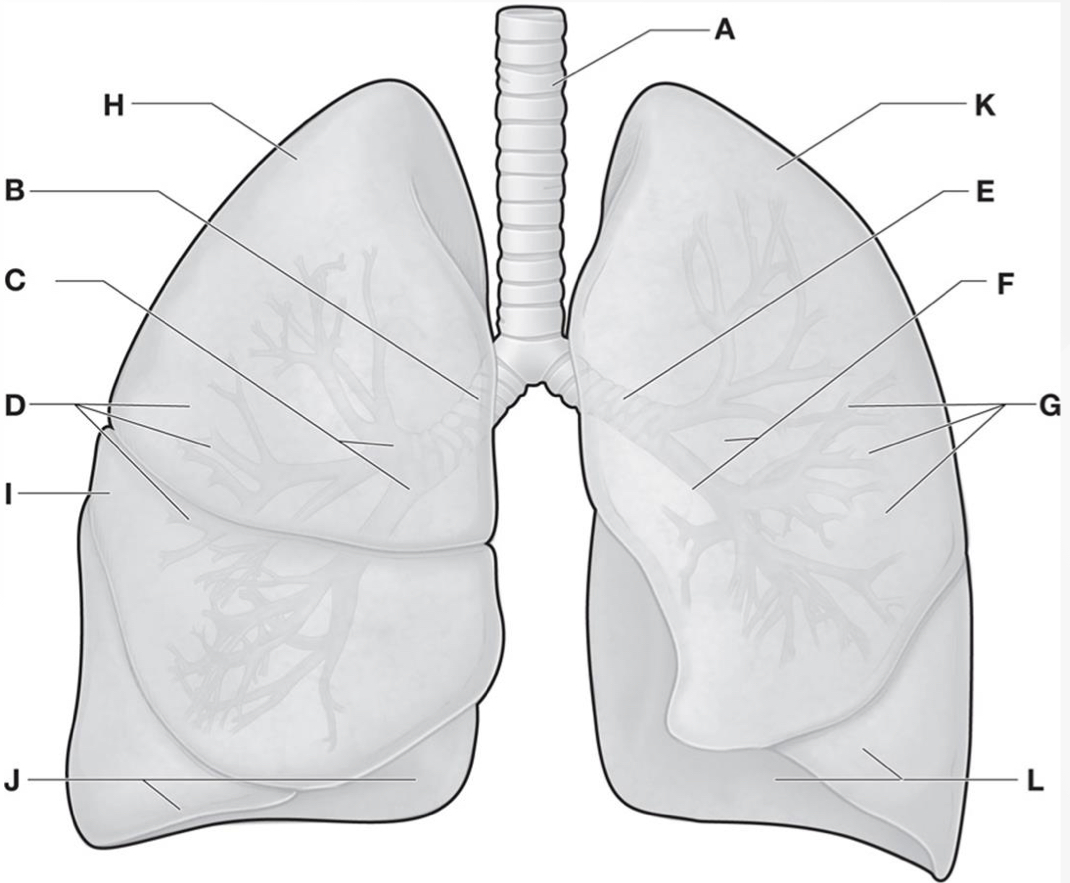

Which letters are the Horizontal & oblique fissures of the Right lung?

A & D

Which letters are the Superior, middle, & inferior lobes of the Right lung?ย

B, C, & E

Which letter is the Oblique fissure of the Left lung?

G

Which letters are the Superior & inferior lobes of the Left lung?ย

F & H